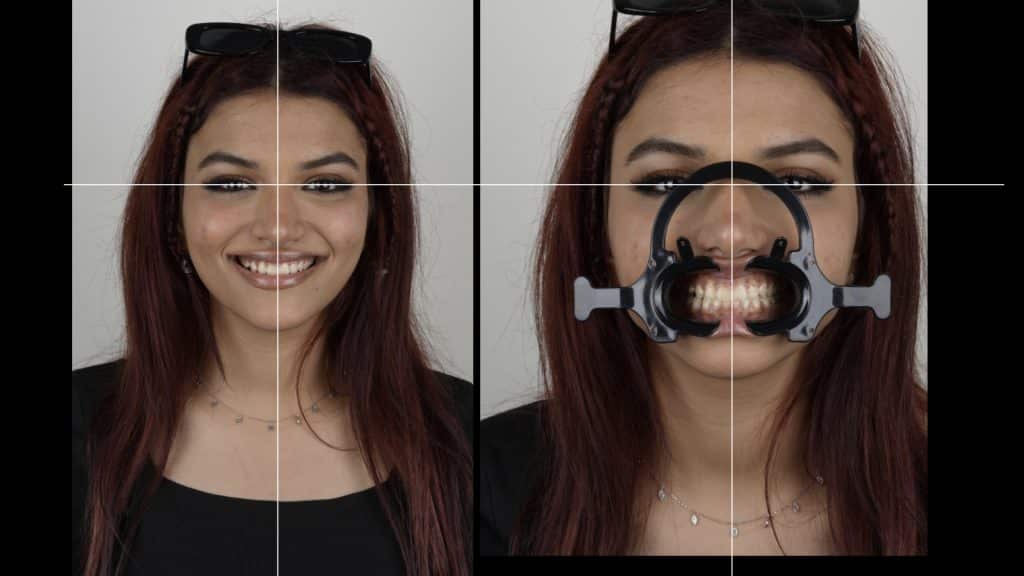

the smile line and papilla line

we measure the length of the right central to calibrate the ruler in Keynote

The design of the teeth (DSD planing)